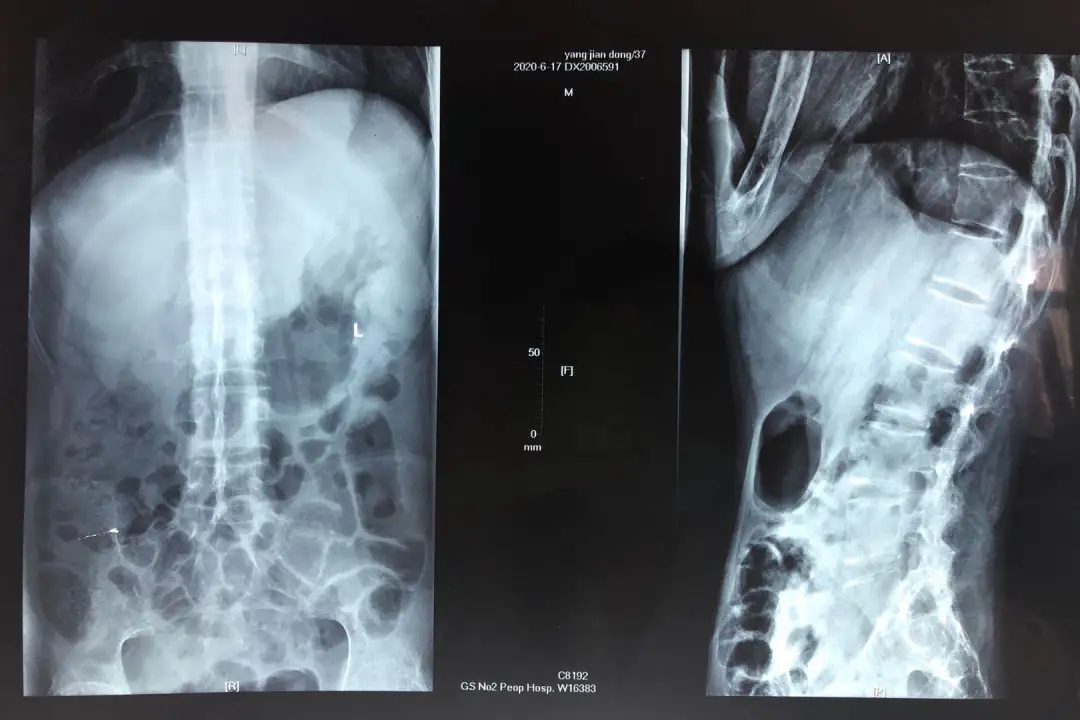

患者37岁,男性,强直性脊柱炎病史9年,近3年来病情加重后膝关节、髋关节强直无法下地活动,多方求医未果,现在患者为求系统性诊治,遂就诊于省二院骨科。由于病程较长,患者体重只有35千克,积极术前多次输血改善营养状况后,拟行在椎管内麻醉下行全髋关节置换术。经麻醉科术前访视患者后评估,患者腰椎间隙融合,无法行椎管内麻醉,决定改用全身麻醉。患者张口度只有1.5横指,龅牙小下颌畸形,舌体肥大,颈部强直,不能后仰及左右活动,属于典型的 困难气道,为了保证患者生命安全,又能有理想的麻醉效果,经麻醉科术前讨论后,决定为患者实施清醒气管插管下全身麻醉。

患者入室后先开放外周静脉输液,检测血压、心率及氧饱和度正常。常规全麻前静脉给予清醒镇静镇痛后,可视喉镜试探下不能看到会厌及气道,局部麻醉药品充分表面麻醉后,纤维支气管镜引导下气管插管顺利。患者在清醒麻醉下可以很好的耐受气管导管,后在常规全麻下比较舒适的完成了手术。